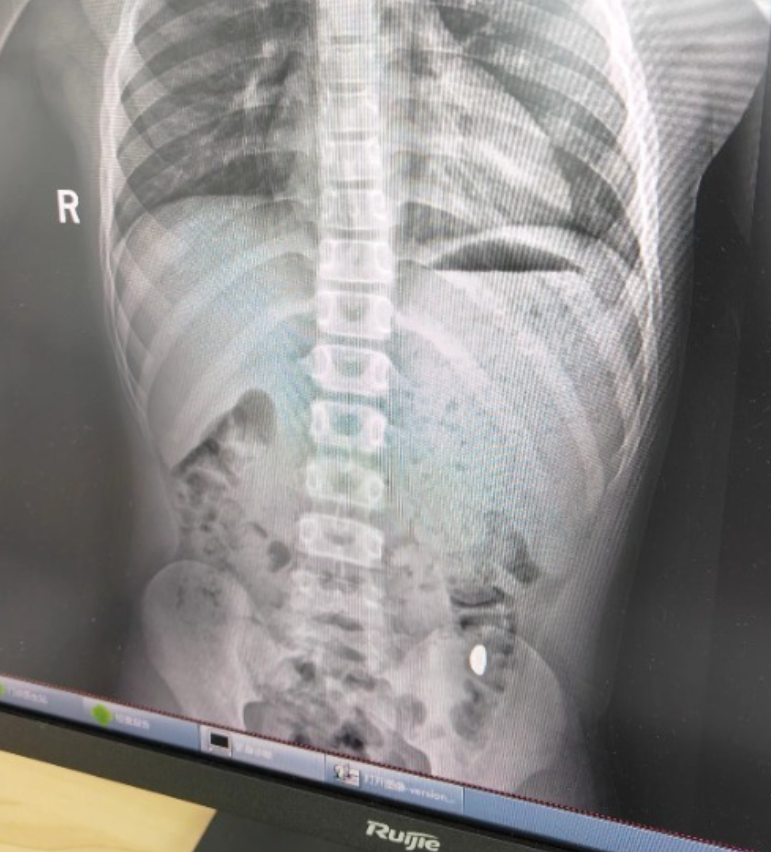

崑山市第五人民醫院門診病歷單顯示,患兒5天前誤吞約10克黃金,其間解兩次大便未發現,無腹痛、嘔吐等症狀,診斷結果顯示胃內有異物。

右下加亮點為金豆。

「上午去的醫院下午就拉出來了。」紀女士說,她把相關內容發佈到社交平臺,引起50多萬人圍觀,她提醒,「大家一定要把家裏的金子妥善存放,千萬別讓熊孩子看到。」